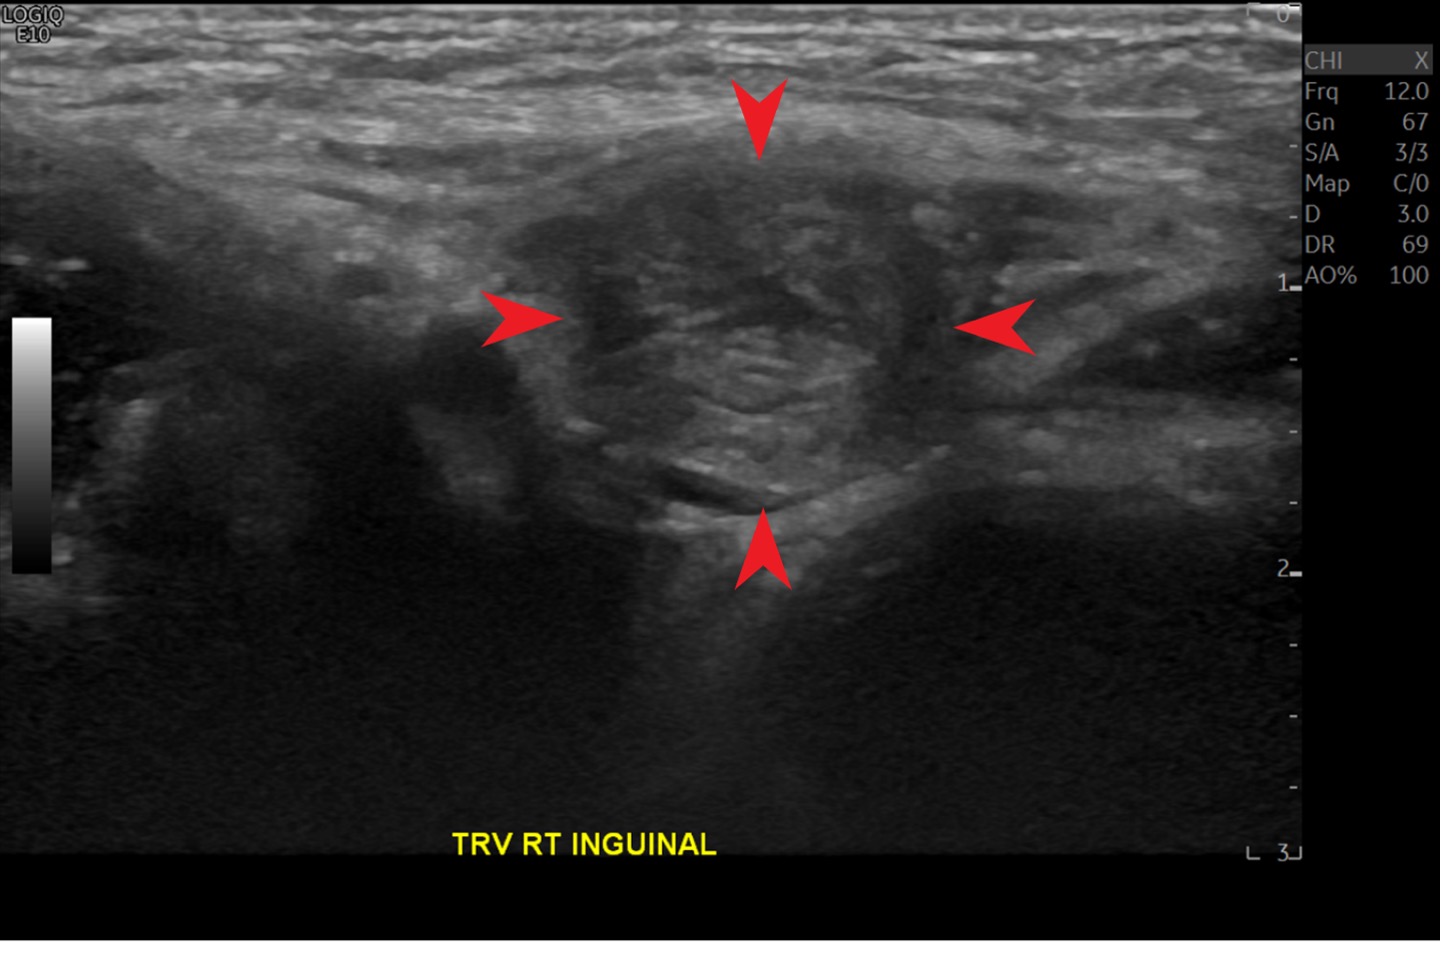

Management and treatment. The patient was taken to the emergency department where the suspected inguinal hernia was reduced after the patient received intravenous pain medication. An inguinal ultrasonography scan was performed, results of which confirmed the presence of inguinal hernias (Figures 1 and 2). The patient was admitted to the hospital with orders not to take any medications or food by mouth and was scheduled for surgery the next morning.

Figure 1. A right inguinal canal with hernia sac is identified (arrows).

Figure 2. A right inguinal canal with hernia sac (red arrows) and the iliac vessels (yellow arrows) are visualized. These are helpful markers when identifying inguinal hernias on the transverse view of the sonogram.